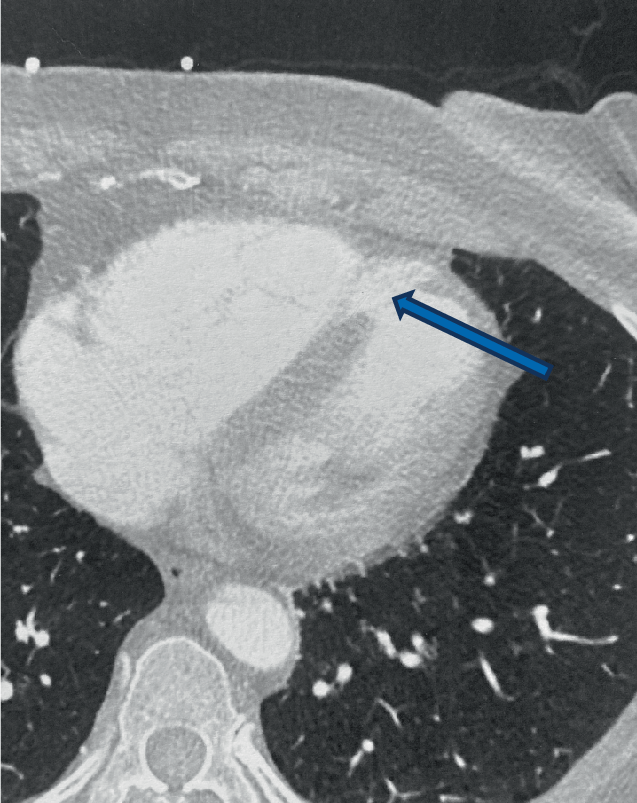

In der unmittelbar durchgeführten Thorax-CT konnten sowohl eine Dissektion der Aorta ascendens wie auch eine relevante Lungenembolie ausgeschlossen werden, es zeigte sich jedoch ein Kontrastmittelübertritt zwischen linkem und rechtem Ventrikel (Abb. 1). Somit musste, bei gleichzeitig bestehendem STEMI der Vorderwand, die Diagnose einer infarktbedingten Ruptur des interventrikulären Septums (Ventrikelseptumdefekt; „Infarkt-VSD“) gestellt werden.

Abb. 1

Thorax-CT mit Kontrastmittelübertritt zwischen linkem und rechtem Ventrikel